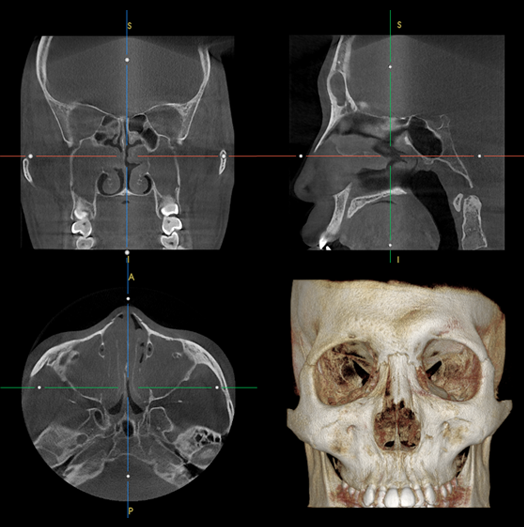

大面積のCTセンサーを搭載して""

23cmx14cm、23cmx24cmの

広いFOVを提供します。

Auto-Stitching""を通じて大面的な撮影へ。

副鼻腔やチョンドゥドン撮影が1回に可能です。